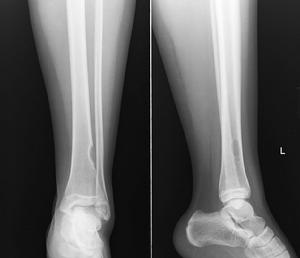

6、發生病理性骨折或變形。

骨腫瘤良性的,早期往往無明顯症狀,若向骨外生長,由於壓迫周圍軟組織,可引起疼痛或功能方面的問題,良性腫瘤,亦可使骨的結構變化,承力作用變弱而發生病理性骨折(這最為常見),骨惡性腫瘤,由於它生長快,往往有肢體明顯腫脹、壓痛,甚至皮膚發熱,血管怒張。

3、骨癌患者早期會發生病理性骨折或變形。